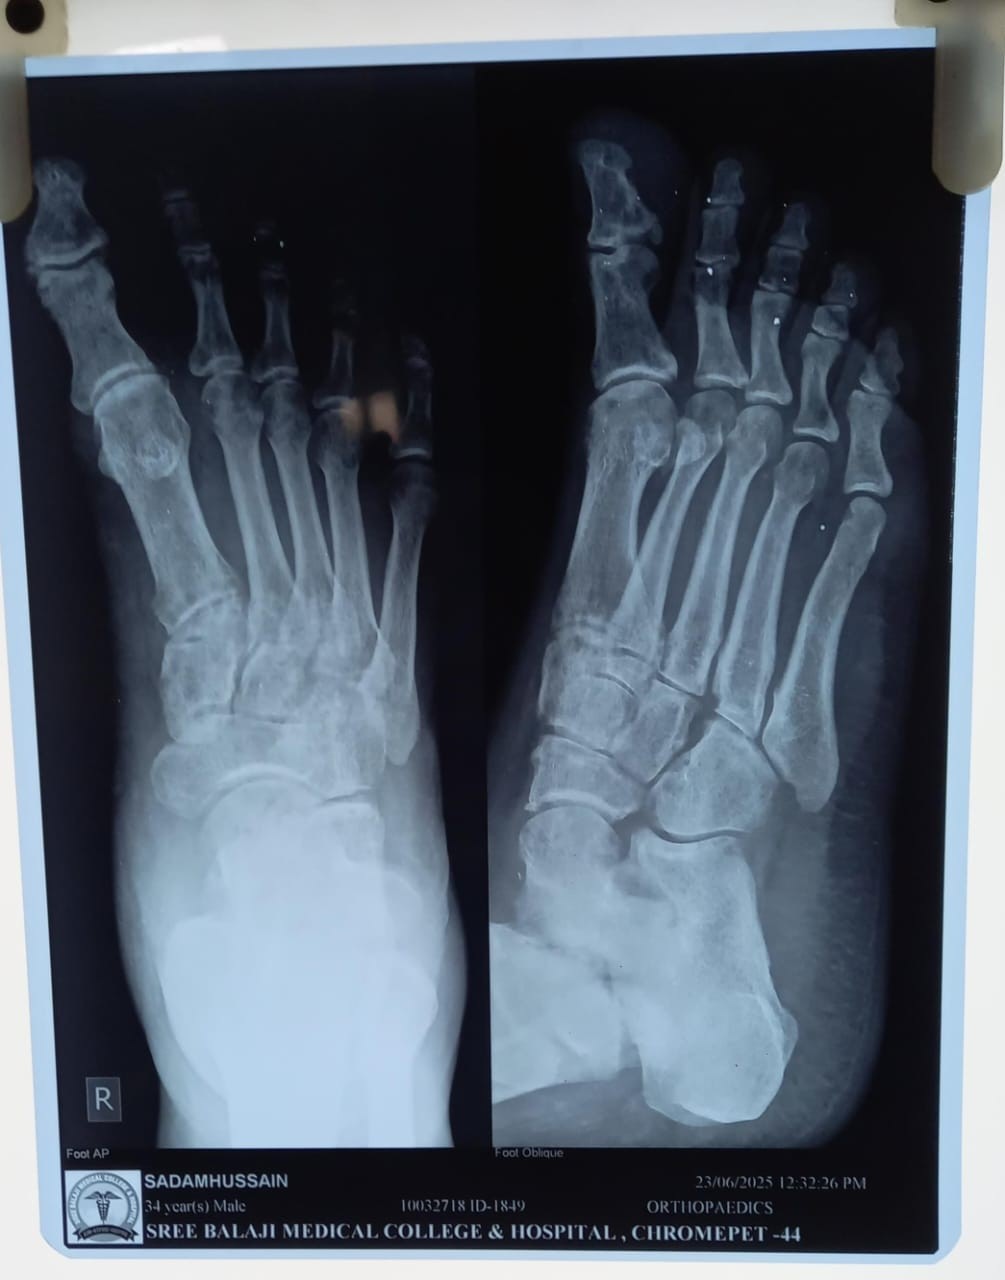

A 34-year-old male presented to our outpatient department with complaints of chronic right ankle pain and difficulty bearing weight for the past several months. He gave a history of a high-velocity RTA 6 months ago, following which he was diagnosed with a talus fracture and managed conservatively with immobilization and non-weight-bearing protocol at another center. The patient resumed weight-bearing pre-maturely due to socioeconomic constraints. Clinical examination revealed mild swelling, tenderness over the anterolateral aspect of the ankle, and restricted range of motion. There was no evidence of neurovascular compromise. Plain radiographs of the ankle showed persistent fracture lines in the talar body region (Fig. 1).

Figure 1: Pre-operative X-ray of talus.